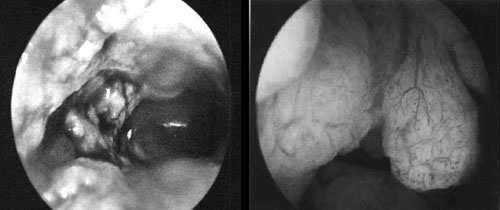

- H εγκυμοσύνη. Aν και μερικοί συγγραφείς(12) χρησιμοποίησαν το υστεροσκόπιο

κατά την κύηση, η κύηση θεωρείται αντένδειξη, διότι είναι υπαρκτός ο κίνδυνος

ρήξης των υμένων, καθώς και η αποκόλληση του πλακούντα εξαιτίας της διάχυσης

του διατατικού μέσου μεταξύ αυτού και της μήτρας.

- Προ ετών, στην κλινική μας, κατά την υστεροσκόπηση μιας ασθενούς 42 ετών με

ινομυωματώδη μήτρα που εμφάνιζε μητρορραγίες, βρέθηκε κύηση 3ου μηνός με ανεγκέφαλο

έμβρυο (εικόνες 10,11).